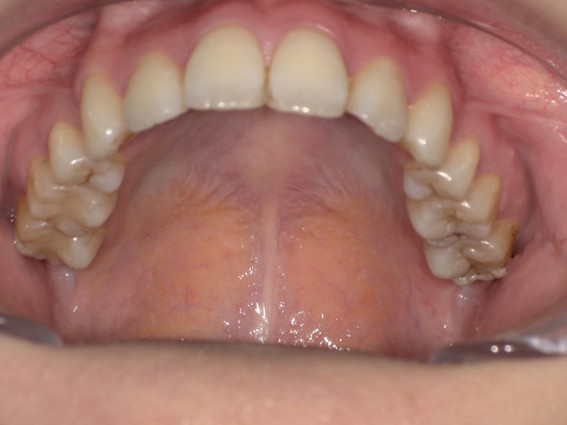

| 主訴 | 前歯が逆に噛んでいるところがある。歯のがたつき。 |

| 治療内容 | 表側ワイヤー矯正、4本抜歯を行いました。 |

| 治療費 | 880,000円+ダイレクトボンディング33,000円(税込) |

| 治療期間 | 30ヶ月 |

| 治療回数 | 30回 |

| 想定されたリスク | 歯根吸収、歯髄壊死、歯髄充血、歯肉退縮のリスクがありました。 |